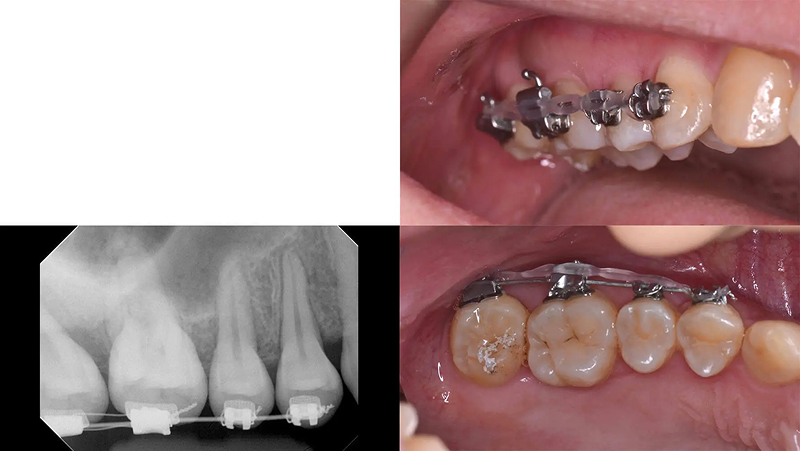

Case03部分矯正とインプラントで歯列を整えた症例

メインテナンスに通っていた患者さんであるとき、左上第2大臼歯のかぶせ物が脱離して来院されました。第2大臼歯は歯根破折をしており、残念ながら予後不良で抜歯と診断しました。元々、第2小臼歯が欠損しており、第1大臼歯がそのスペースに倒れこんでいる歯列不正がありました。この機会に歯列を整えて、インプラントをしましょうと提案しました。承諾していただき、5か月の部分矯正後、インプラントを埋入しました。3年経ちましたが経過は順調です。

初診 2016.1.21

左上7番 歯根破折 ⇒ 抜歯 左上6番 部分矯正開始 2016.2.8

左上6番 部分矯正終了 2016.7.12 ファイナル 2016.9.27

治療後3年 2019.10.12

| 主訴 | 左上1番奥歯の冠が外れた |

|---|---|

| 診断 | 右側アングル1級、左側アングル2級の叢生 |

| 矯正方法 | 矯正用アンカーを用いた部分矯正 |

| 矯正期間 | 5か月・7回 |

| 費用 | 129,000円(税別) |

| 調整料 | 月1回 5,000円(税別) |